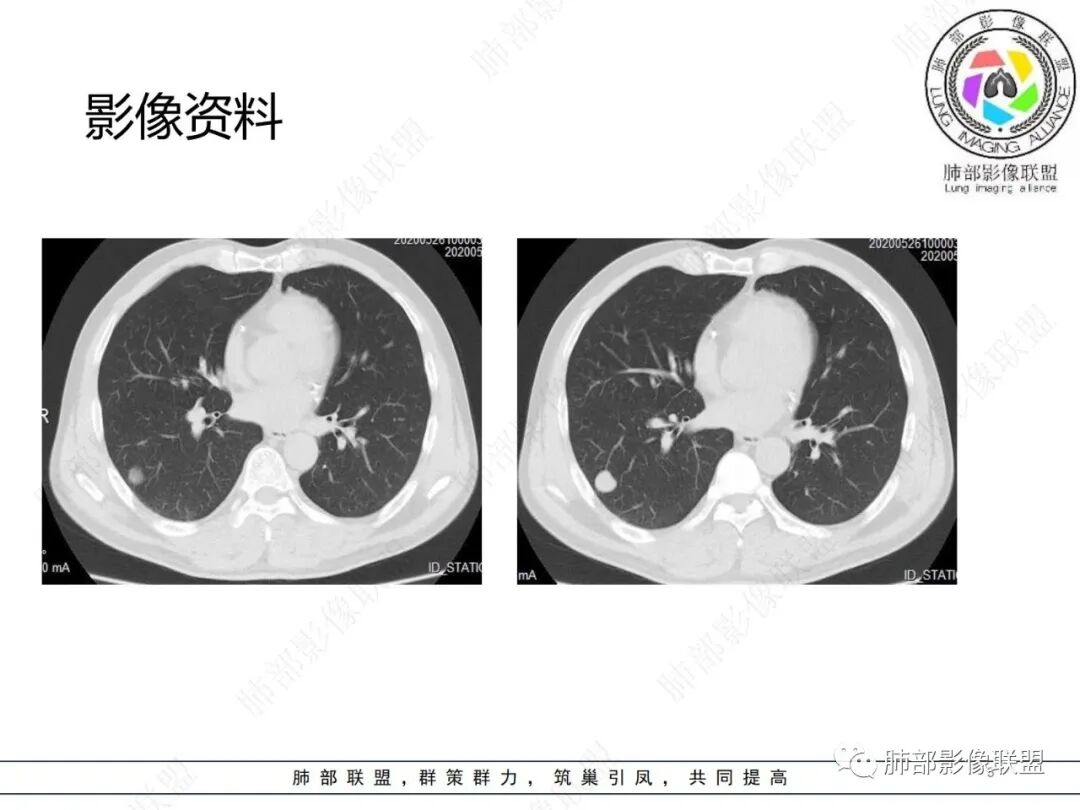

老年男性,右肺下叶胸膜下结节,膨胀性生长,边缘清晰,无胸膜凹陷,增强可见环形强化,内见低密度区,考虑炎性肉芽肿病变,结核可能。

老年男性,右肺下叶实性结节,边缘膨隆分叶,增强后轻度不均匀强化,考虑良性肉芽肿结节,建议随诊观察除外腺癌

右肺下叶实性结节,边缘光滑,无毛刺分叶,支持肉芽肿性病变

中年男性,右肺实性结界,边界清楚,光滑,见低密度区,考虑肉芽肿性病变?错构瘤?

边缘光滑,密度不均,提示良性病变可能性大,错构瘤?

右肺下叶近胸膜处类圆形结节,边缘光整,浅分叶,挂果,周围黑边,密度不均,轻度不均匀强化,考虑错构瘤,鉴别腺癌

右肺下叶结节,整体光整,浅分叶,强化低,考虑良性,错构瘤?

老年男性查体,右下肺类圆形高密度影,边缘光滑清楚,强化不明显,看着血管贴边,首先考虑良性肿瘤,PSP,错构瘤,鉴别肉芽肿性病变,腺癌

老年男性,右肺下叶结节,边缘膨隆分叶、浅分叶,增强后边缘强化,血管贴边,首先考虑PSP,鉴别腺癌,肉芽肿结节。

男,51。右肺下叶孤立实性结节,边界清,边缘少许磨玻璃,周围气肿带,浅分叶,平扫内见点状低密度,强化不明显。考虑良性结节,错构瘤>炎性肉芽肿鉴别腺癌。

右肺下叶胸膜下一类圆形实性结节,边缘似乎有点磨玻璃晕感,边缘圆钝,浅分叶,血管贴边包绕,增强后轻度强化,矢状面显示病灶后方有条线样尾巴,结节形态及强化可以符合错构瘤,但血管包绕,病灶后方的小尾巴又有点让人不安。考虑恶性,腺癌可能,鉴别错构瘤。

此病例中结节,与支气管无关系,边缘清晰,形态规则,缺乏张力,未见典型的分叶及毛刺,病灶周围磨玻璃为部分容积效应所致,肺门纵隔未见肿大淋巴结,良性病变可能性较大,肺部的良性肿瘤中,最常见的是错构瘤,其次是硬化性肺细胞瘤(PSP),第三是孤立性纤维性肿瘤(SFT)。

恶性病灶容易想到孤立转移灶或大细胞肺癌等,病史以及强化特点等不大支持。